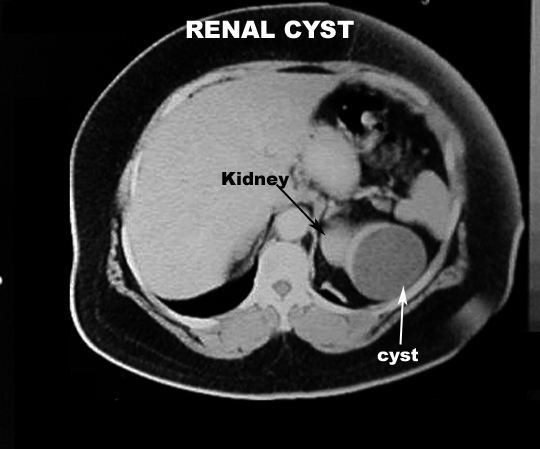

Genito Urinary Case 1: Renal Cyst

Spine x-ray shows severe osteoarthritic changes of lower lumbar spine. Incidentally there is a soft tissue mass overlying left renal area. Workup of this incidental mass turned out to be Simple Renal cyst.

Simple Renal Cyst:

Contrast CT characteristics: